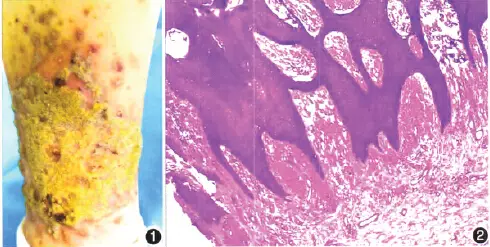

【查体】各系统检查未见异常。皮肤科检查:臀部、双侧内踝上方、足背数个褐色、大小不等的疣状增生斑块,大的10cm×8cm,边界清,形状不规则,表面干燥,无毳毛;斑块周围散在0.2cm×0.2cm丘疹;足背及内踝可见数个褐色线圈样皮损,边缘略隆起。